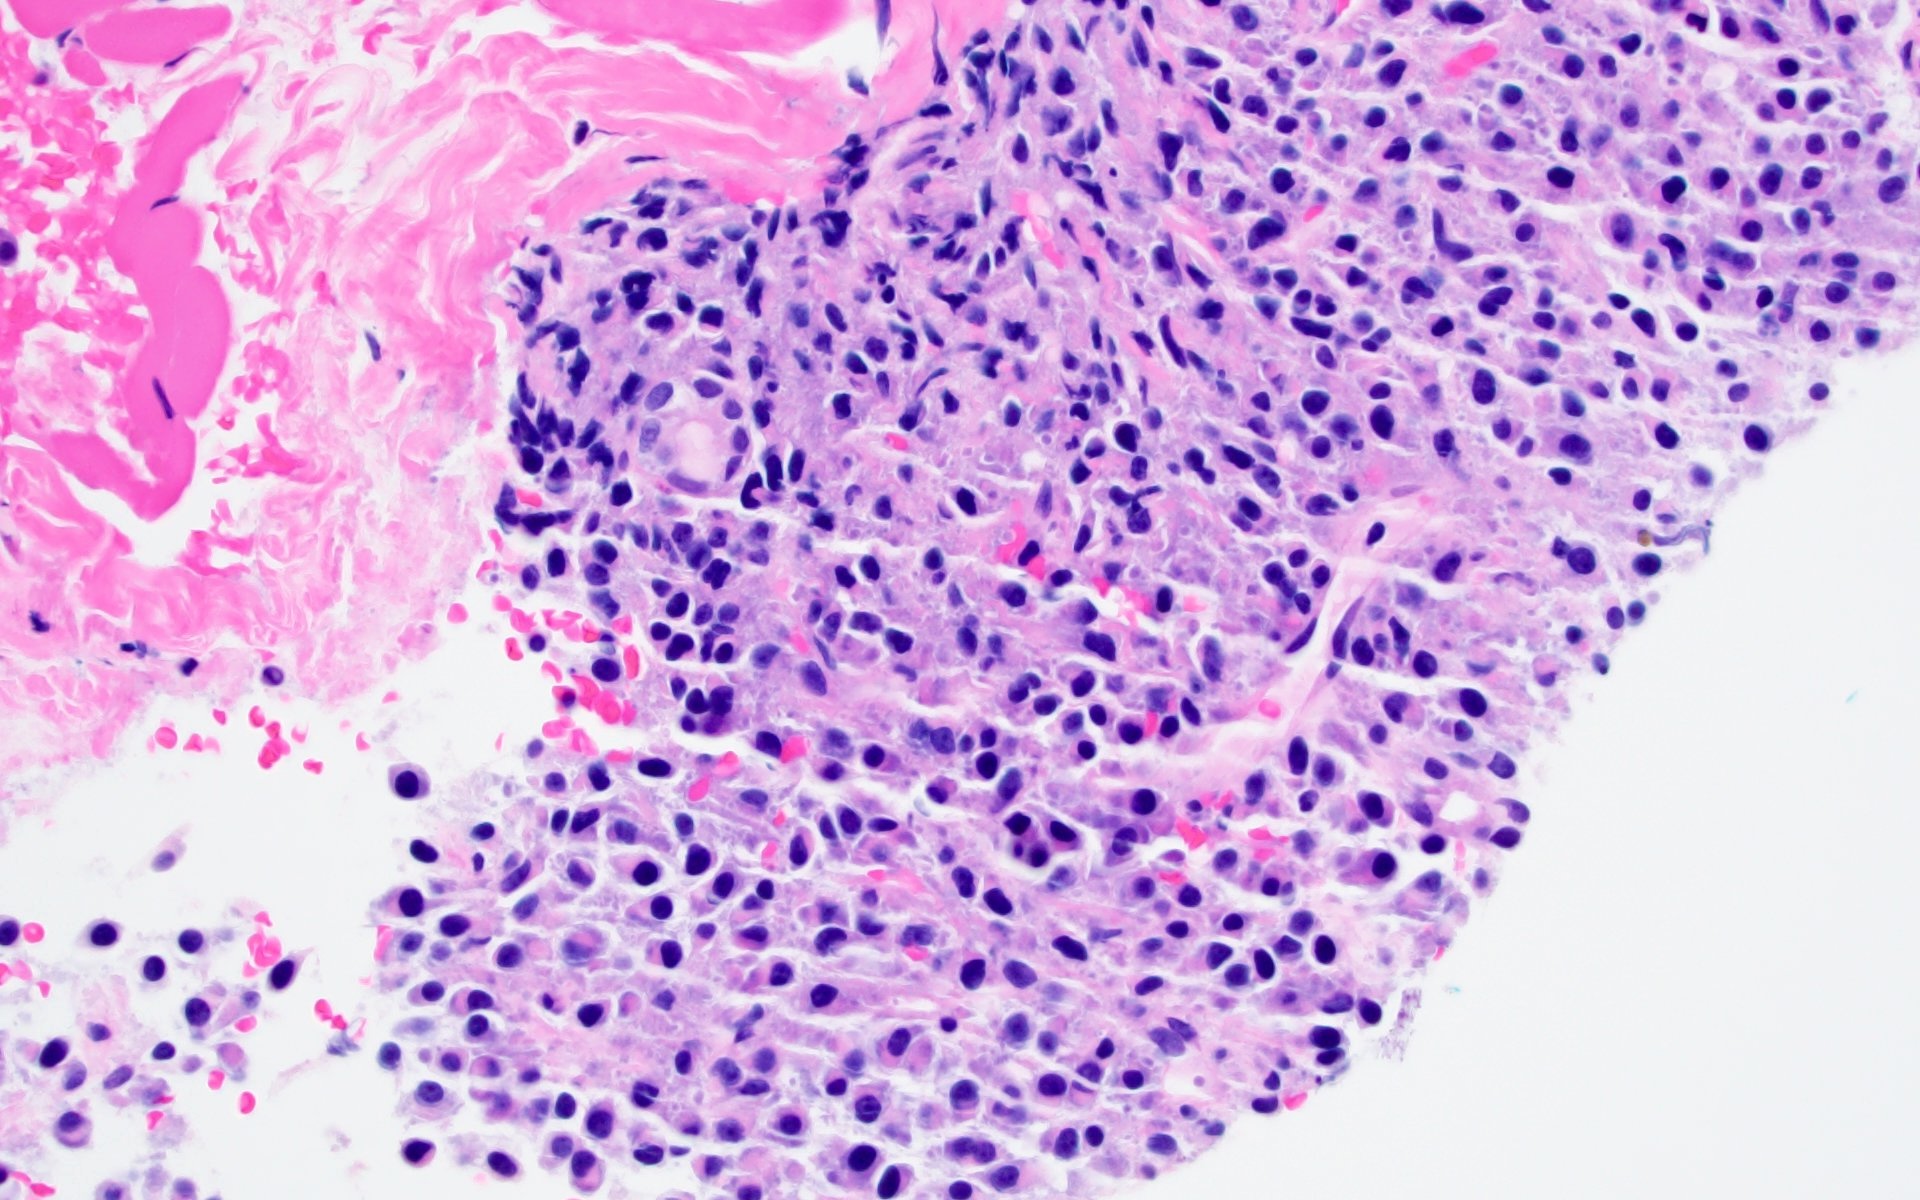

- Sheets of plasma cells with varying morphology ranging from normal appearing to large atypical plasma cells with prominent nucleoli to plasmablastic or anaplastic morphology (Am J Clin Pathol 2001;115:119, J Clin Oncol 2012;30:e91, Skeletal Radiol 2018;47:995)

- Russell or Dutcher bodies may be seen

- Associated amyloid deposition (Ann Diagn Pathol 2015;19:117)

Microscopic (histologic) images

A 43 year old man presents with nasal obstruction and epistaxis. Imaging showed a 2.2 cm nasopharyngeal mass. Nasopharyngeal and bone marrow biopsies were performed (see images above). Which of the following risk factors in this patient increases the chances of progression to multiple myeloma?

B. Bone marrow involvement is present in this case, which increases the risk of progression to multiple myeloma. Answers A, C and D are incorrect because the patient is young and the tumor size is < 5 cm with bland morphology (not plasmablastic / anaplastic), so none of the factors accounted for by these options increase risk of progression to multiple myeloma.